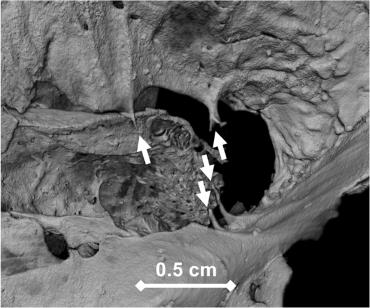

Its main aim resides in the identification and study of reliable skeletal markers of respiratory and airborne diseases (which mostly take the form of osteoblastic or osteoclastic activity, anatomic structural remodeling and bone sclerosis). This project also endeavors to assess the diagnostic value of the said skeletal markers in clinical settings